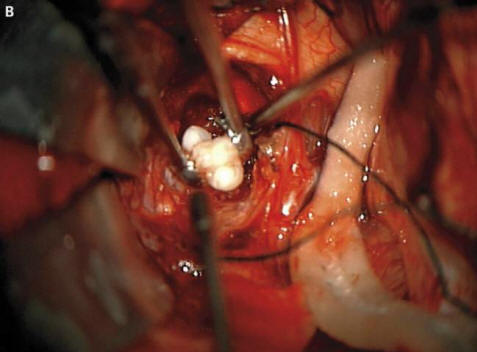

Chirurgové z amerického státu Maryland museli jeden utratit nejtěžších operací ve své praxi. Čtyřměsíční rodiče chlapci vydali poplach a poté šli k doktorům všimli si, že hlava jejich dítěte roste příliš rychle. Lékaři provedl sken a zjistil, že v mozku pacienta vyrostl zub.

Foto z otevřených zdrojů Jak chirurgové vysvětlili vystrašeným rodičům a onkologové to bylo způsobeno tvorbou vzácného vrozeného tumory – kraniofaryngiomy, píše New England Journal of Medicine. Tento novotvar ve velké většině případů benigní však může růst na velikost míče golf a způsobuje pokles čichu, zhoršeného sluchu a zraku, a také zvyšuje intrakraniální tlak. Výzkumníci vždy podezření, že tyto nádory, které se objevují u dítěte již v r těhotenství, vytvořené ze stejných buněk jako zuby, protože zjistili velké hromadění vápníku, ale skutečně vytvořený zub před tímto případem, který nemohou najít započítal.

Chirurgové úspěšně odstranili fotografii z otevřených zdrojů The tumor, chlapec, říkali, si vede dobře. To je ale zub vyrostl ve své hypofýze, ale narušil mozek, zejména, správná produkce hormonů – pacient je bude muset vzít dříve konec života. Tento případ se může právem pyšnit místem seznam nejpodivnějších operací prováděných onkology. Mezitím v roce mladý muž z Íránu, který musel léčit chlupaté oči. Téměř se mu objevil podivný nádor v jeho oku ihned po narození, ale ve věku 19 let se výrazně zvýšila v roce 2005 o velikosti (do 0,6 cm) a zabránila tomu, aby byla víčka navíc uzavřena ztuhlé vlasy začaly růst. Lékaři odstranili nádor a zjistili, že toto je limbální dermoid – obvykle velmi vzácný benigní vzdělání. Podle lékařů v tom případě pokud mladý muž pokračoval v tažení léky, jeho otok mohl nejen pěstovat vlasy, ale také se začal potit: postupem času u novotvarů se často objevují odpovídající žlázy.